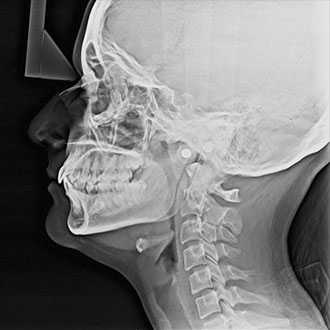

Cephalometric radiography provides a complete view of the dento-maxillo facial region. The functionally designed and easy to use head positioner ensures accurate patient positioning in lateral a.p and p.a technique.